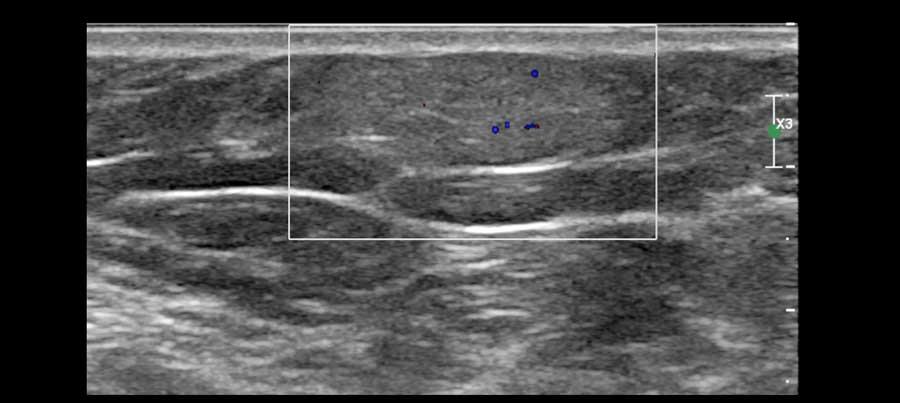

Đôi khi một phần của nang không có hình ảnh trống âm mà lại giảm âm hoặc tăng âm.

Điều này có thể là kết quả của mủ hoặc các mảnh vụn, nhưng cũng có thể là một khối u trong nang như trong các hình ảnh này.

Khối u trong nang là hiếm gặp.

Khi thấy có mạch máu trên siêu âm Doppler màu thì đó là khối u trong nang, có thể lành tính hoặc ác tính.

Đây là một khối u có thành phần dạng nang chứ không phải là một nang đơn thuần.

Trong trường hợp không có dòng chảy trên siêu âm Doppler màu và không có tín hiệu âm mức độ thấp di chuyển khi thay đổi tư thế bệnh nhân, cần thực hiện chọc hút để phân biệt giữa nang phức tạp và khối đặc.

Mủ và các mảnh vụn có thể được hút ra, khác với khối u.

Trong trường hợp này, sinh thiết xác nhận là ung thư biểu mô trong nang.

Đây là một trường hợp ung thư vú khác có thành phần dạng nang.

Lưu ý thành phần đặc lớn với dòng chảy trên hình ảnh Doppler.